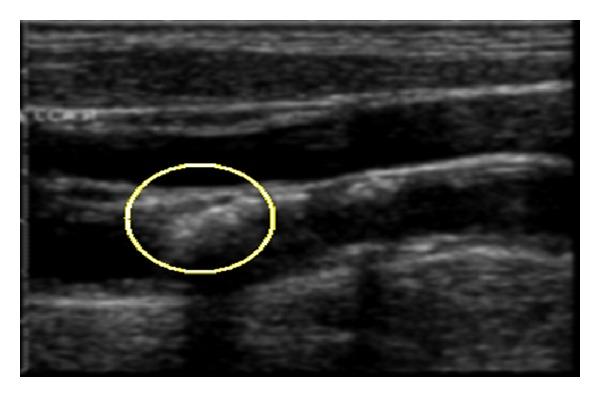

Automatic Characterization of the Physiological Condition of the Carotid Artery in 2D Ultrasound Image Sequences Using Spatiotemporal and Spatiospectral 2D Maps.

A novel method for characterizing and visualizing the progression of waves along the walls of the carotid artery is presented. The new approach is noninvasive and able to simultaneously capture the spatial and the temporal propagation of wavy patterns along the walls of the carotid artery in a completely automated manner. Spatiotemporal and spatiospectral 2D maps describing these patterns (in both the spatial and the frequency domains, resp.) were generated and analyzed by visual inspection as well as automatic feature extraction and classification. Three categories of cases were considered: pathological elderly, healthy elderly, and healthy young cases. Automatic differentiation, between cases of these three categories, was achieved with a sensitivity of 97.1% and a specificity of 74.5%. Two features were proposed and computed to measure the homogeneity of the spatiospectral 2D map which presents the spectral characteristics of the carotid artery wall's wavy motion pattern which are related to the physical, mechanical (e.g., elasticity), and physiological properties and conditions along the artery. These results are promising and confirm the potential of the proposed method in providing useful information which can help in revealing the physiological condition of the cardiovascular system.